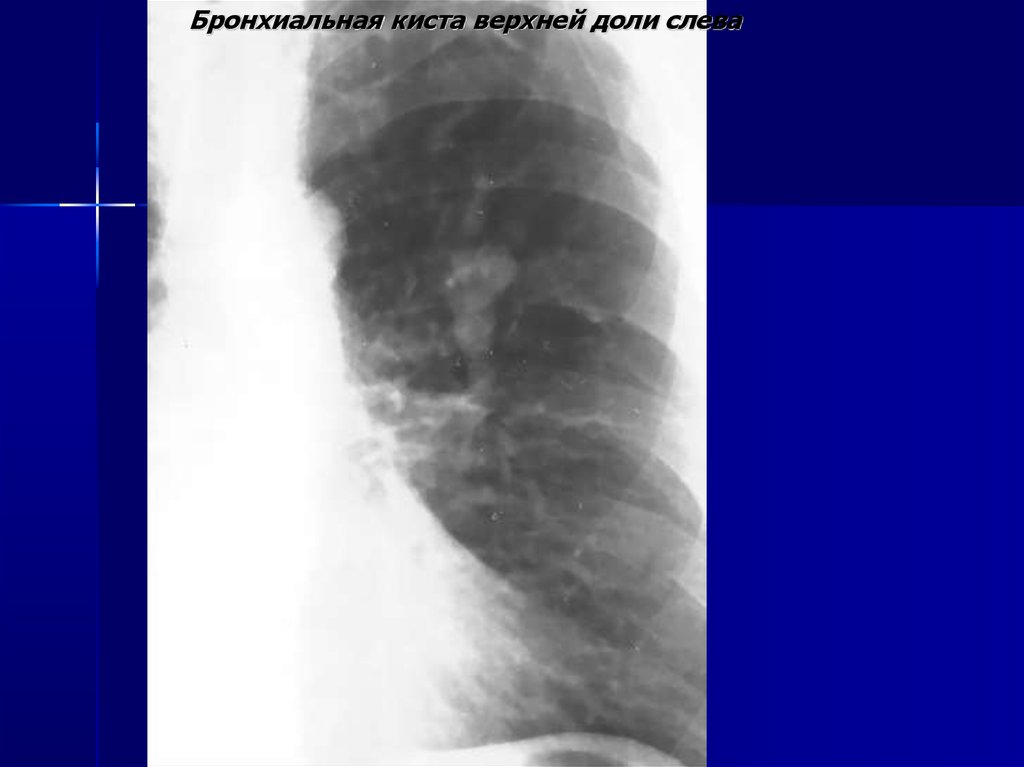

Бронхиальная киста верхней доли слева